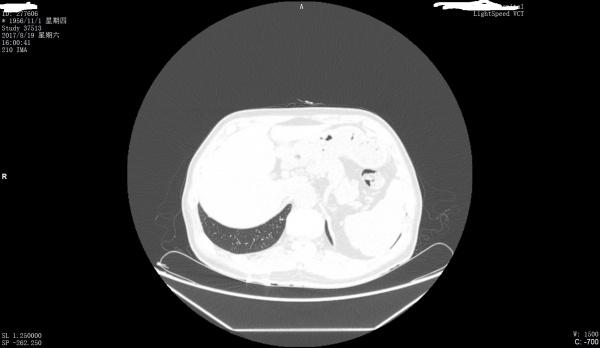

看看是否左膈肌出现胸腹膜裂孔疝